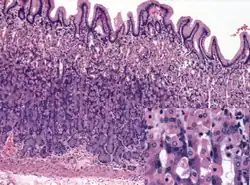

Histology of normal fundic mucosa. Fundic glands are simple, branched tubular glands that extend from the bottom of the gastric pits to the muscularis mucosae; the more distinctive cells are parietal cells. H&E stain.

Within the body and fundus of the stomach lie the fundic glands. In general, these glands are lined by column-shaped cells that secrete a protective layer of mucus and bicarbonate. Additional cells present include parietal cells that secrete hydrochloric acid and intrinsic factor, chief cells that secrete pepsinogen (this is a precursor to pepsin- the highly acidic environment converts the pepsinogen to pepsin), and neuroendocrine cells that secrete serotonin.[25]